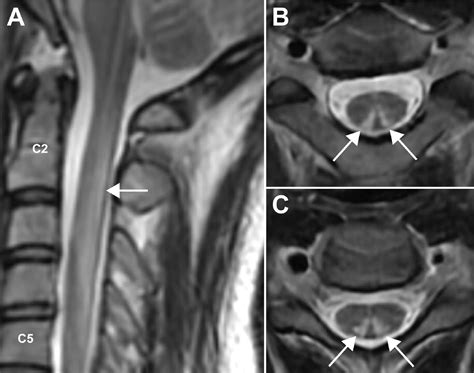

• Magnetic Resonance Imaging (MRI): To visualize the spinal cord and brain for signs of degeneration.

• subacute combined degeneration on mri